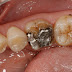

全瓷齒雕---咬合貼片

咬合貼片是全瓷3D齒雕的一種應用方式,可針對在後牙整體狀況不錯,而僅在咬合面有磨耗,大範圍蛀牙或鈣化不全的情形下使用。      傳統的材質若要改善上述的問題,可能唯一的方式就是要做整顆的牙冠,牙冠當然是堅固耐用,只可惜要磨掉較大量的齒質才能製作。     ...